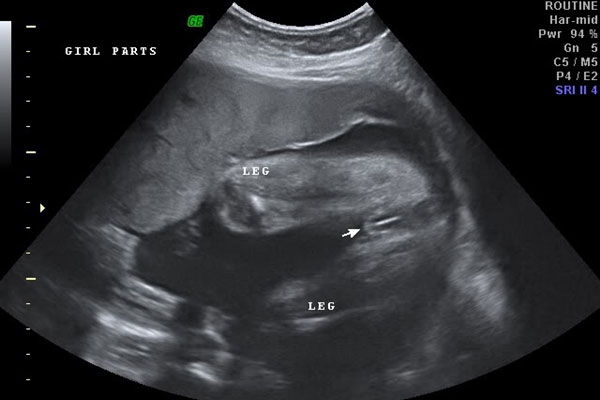

四维彩超男女腿部间的区别图

按照胎儿正常的发育来看,生殖器发育一般会在18-20周正式开始发育,特别是男孩的小JJ,一般要等到18周左右才会正式下来,而女孩的话这个时候双腿间还是平平的。根据b超技术来看,24周做四维彩超的时候是可以清晰明确看到男孩女孩的生殖器的,此时男女腿部间的区别很好区分。

如果是男孩会看到凸起的一坨,有的还会看到上面的小尖尖,女孩则是圆圆的一坨,有点鼓包样。四维彩超的时候男孩胎儿的生殖器已经很好区分了,女孩的看起来稍微不好区分。在24周之前男孩生殖器这里一般会有圆球或者亮点,女孩胎儿在24周的时候看双腿间的话会有白线,一般都是三条白线,代表的是女孩的大小***。

因此,如果大家有幸看到胎儿腿部间有凸出的,就像是小乌龟一样的,那十有八九怀的是男孩,反之如果腿部间平平的甚至还会看到三条白线的话一般就是女孩了。当然,提醒一下各位妈妈们,这个时候胎儿胎动活跃,角度和体位也会随时变换,有时候很容易将手指或者脐带弄混淆,这个时候就要看生殖器的反光和亮点来区分了。